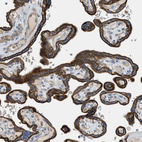

Immunohistochemical staining of human placenta shows strong positivity in trophoblastic cells.